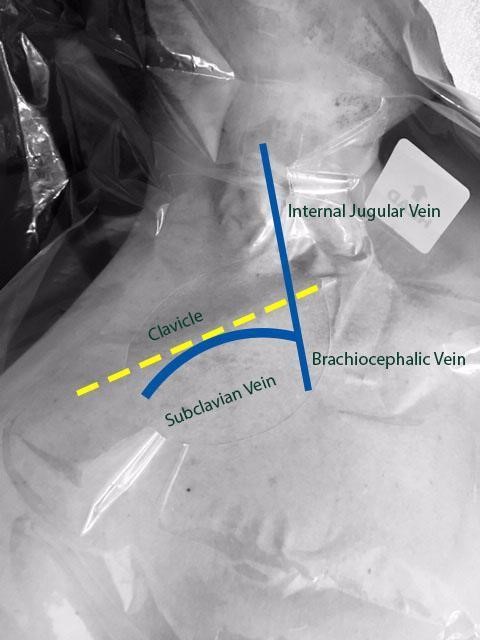

Central venous catheters play an important role in the care of critically ill patients. The subclavian vein (SCV) is a deep central vein that is an extension of the axillary vein as it courses beneath the clavicle starting at the lateral border of the first rib before joining the internal jugular vein (IJV) medially under the clavicle. SCV cannulation offers several advantages when compared to the alternative sites, including fewer infectious complications, fewer cases of symptomatic deep venous thrombosis, and increased patient comfort.1 Despite the advantages that SCV central line offers, landmark-guided cannulation of the SCV can be associated with many complications such as arterial puncture, hematoma, pneumothorax, hemothorax, catheter malposition, and nerve injury.2

Figure 1. Anatomy of subclavian vein as it courses underneath the clavicle and merges with the internal jugular vein to form the brachiocephalic vein.